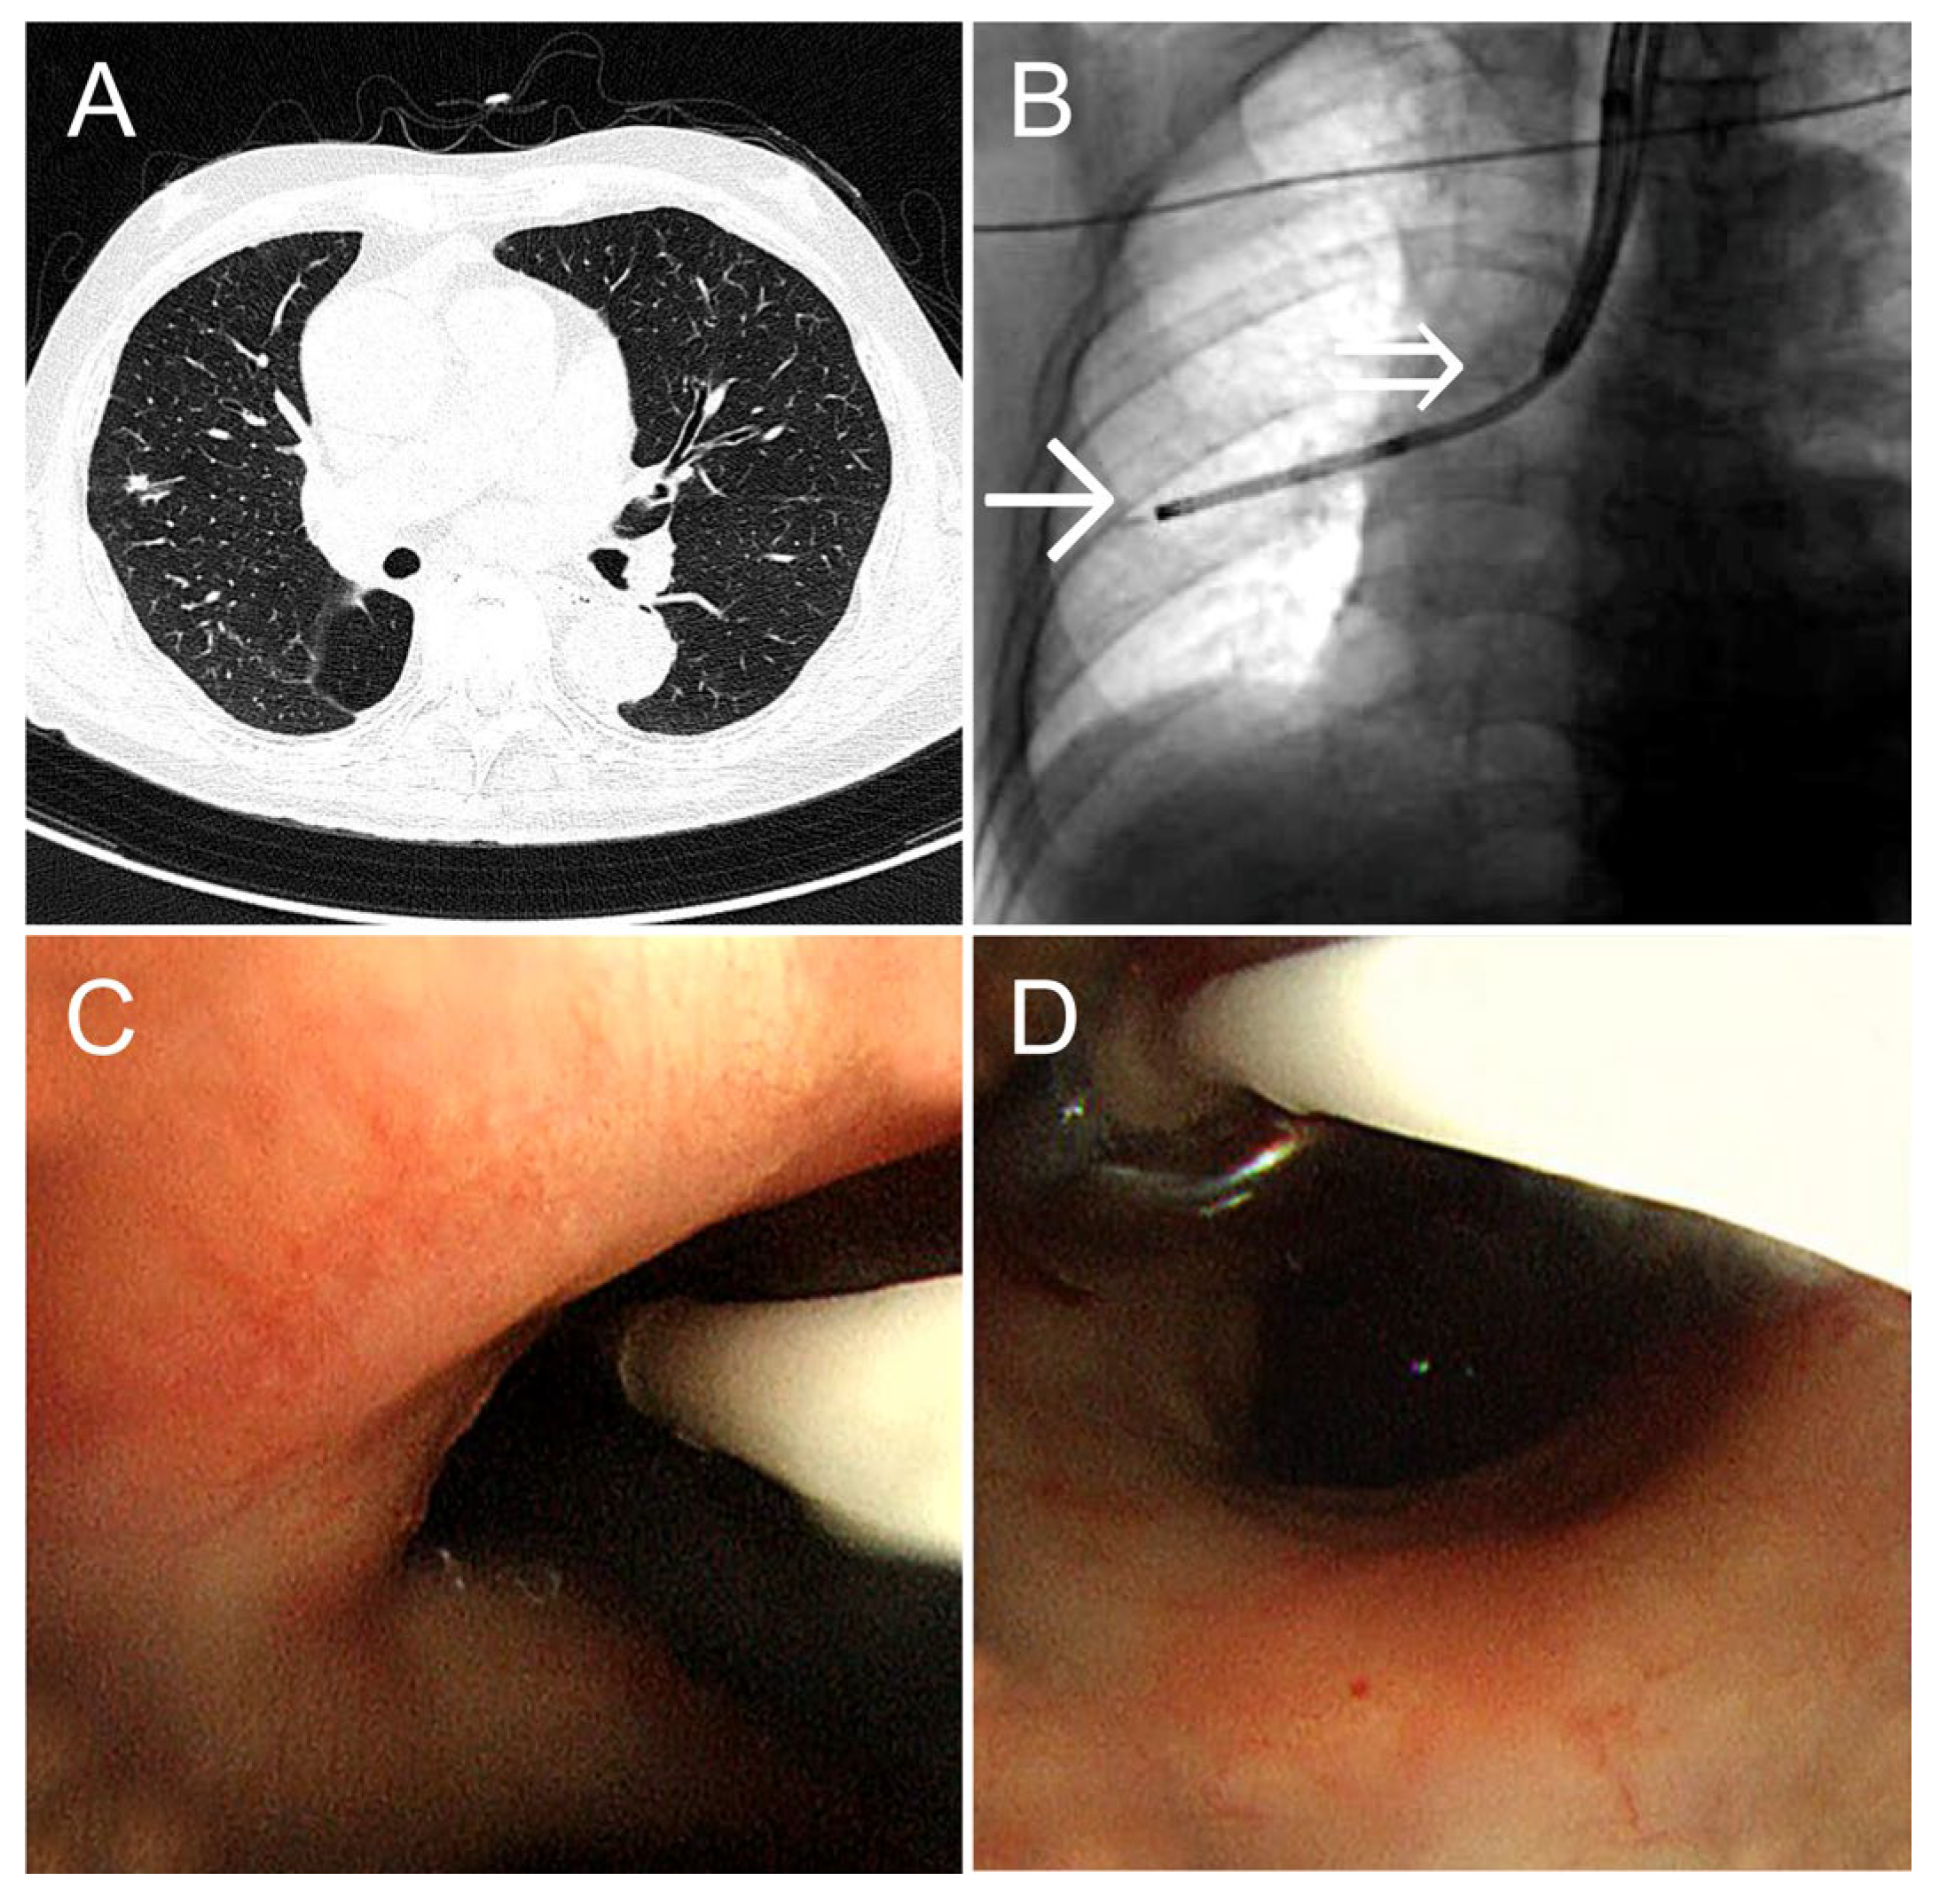

An 84-year-old man (height: 157 cm; weight: 54 kg) with comorbid heart failure and chronic obstructive pulmonary disease underwent a right lower lobectomy for right lower lobe squamous cell carcinoma. Postoperative follow-up computed tomography (CT) revealed a 0.6-cm solid nodule in the S3 periphery of the right upper lobe. A detailed examination was conducted. Fixing the balloon in the right upper lobe using the conventional method was deemed difficult; therefore, we selected the dual-scope method. An ultrathin bronchoscope was guided to the lesion, and cryobiopsy was performed using our method. Bleeding was completely controlled by 5 min of balloon occlusion at the right upper lobe bronchus. TBLC was performed in 31 min, maintaining oxygen saturation (SpO2) at 99% (Figure 2). The diagnosis was primary lung squamous cell carcinoma.

Figure 2. (A) A 0.6-cm solid nodule is observed in the right upper lobe B3a iβ. (B) X-ray fluoroscopy image taken during cryobiopsy. The single arrow (→) indicates the tip of the ultrathin bronchoscope, and the double arrow (⇒) indicates the tip of the therapeutic bronchoscope. (C) Bronchoscopy view immediately before cryobiopsy. The ultrathin bronchoscope and balloon catheter are observed simultaneously, showing that the balloon catheter can be easily guided through the working channel. (D) After the ultrathin bronchoscope is removed, the balloon catheter is inflated under endoscopic visualization. The position of the balloon and the moment of inflation can be confirmed using the endoscope, allowing for reliable hemostasis.